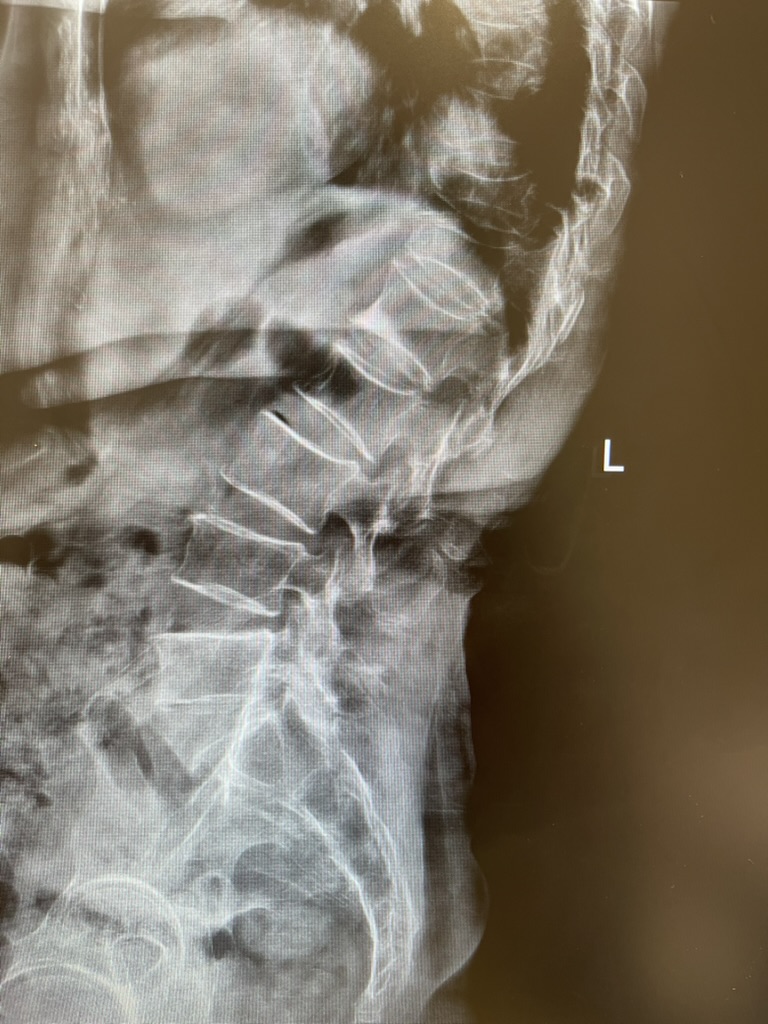

4. การตรวจมวลกระดูก (Bone Densitometry

– DXA): เป็นการใช้รังสีเอกซเรย์ระดับต่ำมาก สแกนดูที่

“กระดูกสันหลัง” และ “ข้อสะโพก”

ซึ่งเป็นจุดที่อันตรายที่สุดถ้าหัก ใช้เวลาเพียง 10-15 นาที ไม่เจ็บเลยครับ